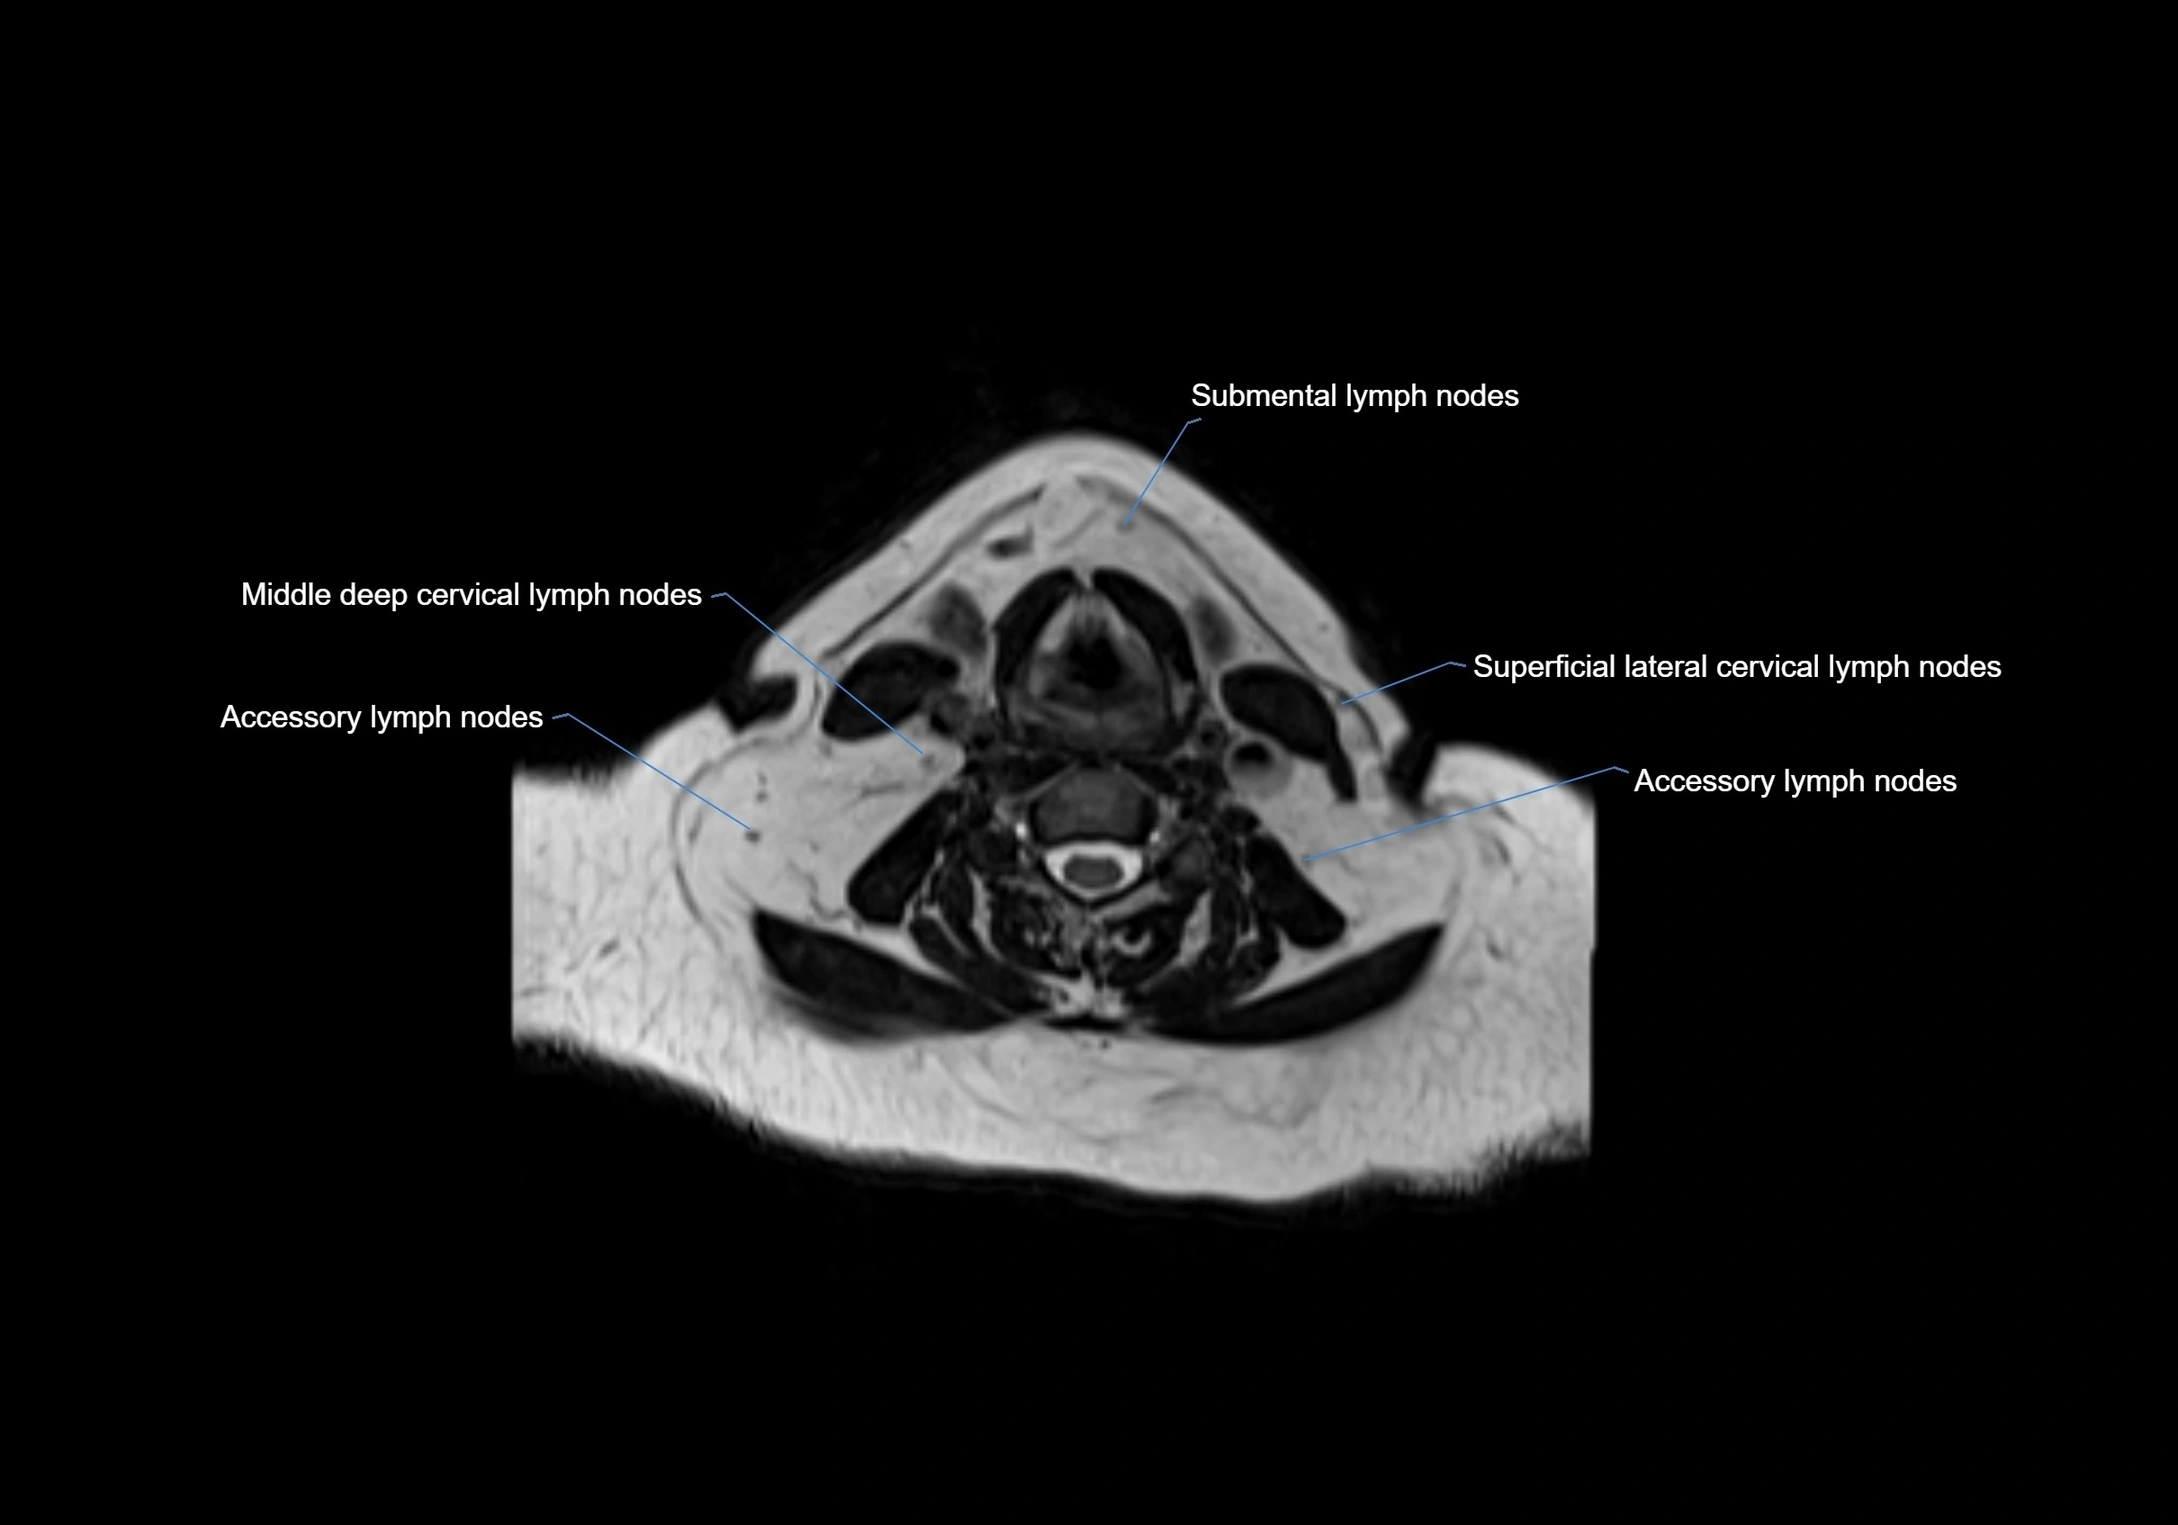

Accessory lymph nodes

Accessory lymph nodes are small, secondary lymph nodes located along the main facial and cervical lymphatic chains, often adjacent to primary lymph nodes, such as preauricular, submandibular, or occipital nodes. They are typically less than 5 mm in diameter, embedded within subcutaneous fat or connective tissue, and may be variable in number and location. These nodes provide additional filtration and immune surveillance for lymph collected from the face, scalp, and neck regions. Accessory lymph nodes are usually non-palpable in healthy individuals but may enlarge in response to infection, inflammation, or metastasis, making them clinically significant.

Location

• Found along primary lymph node chains, including preauricular, submandibular, parotid, and occipital regions

• Embedded in subcutaneous fat or superficial fascia, often lateral or posterior to primary nodes

• Variable in number; may occur unilaterally or bilaterally, depending on individual anatomy

MRI images

image